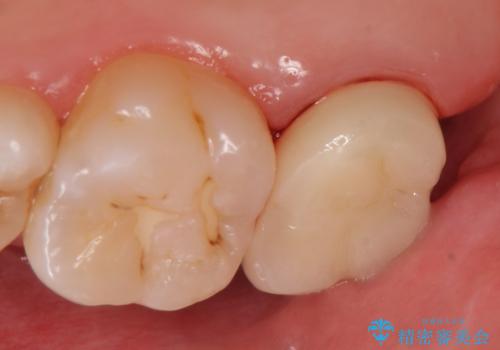

オールセラミッククラウン 鈍痛が続く奥歯の治療

- 他院にて右上7番目の歯の根管治療を行ったが鈍い痛みが治まらないので診て欲しいといらっしゃった方の症例です。

再根管治療を行い症状の消失を確認後、オールセラミッククラウンによる補綴を行いました。

今回用いたオールセラミッククラウンはジルコニアフレームという白い素材の上にセラミックを盛っているため、審美性が非常に高いのが特徴です。

また、ジルコニアは人工ダイヤモンドの材料にも使われているほど高い強度を持っており、そのためオールセラミッククラウンは審美性だけでなく、奥歯やブリッジの補綴も可能とするクラウンです。